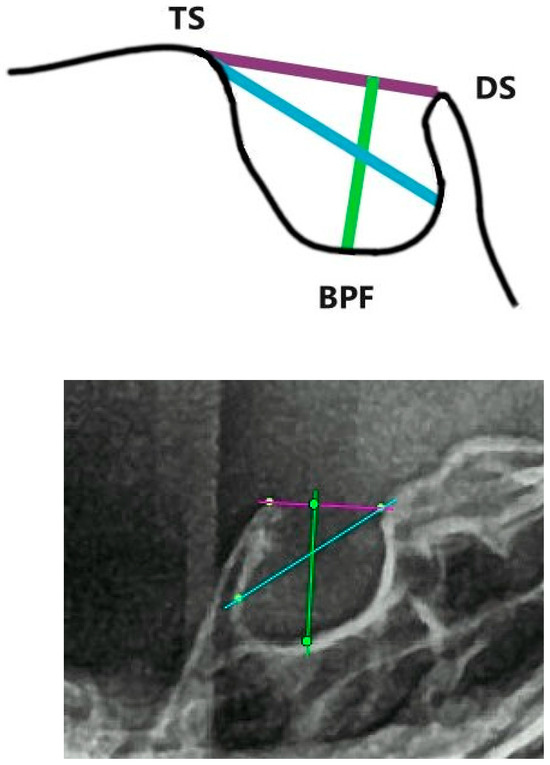

2.2. Dimensions of Sella Turcica